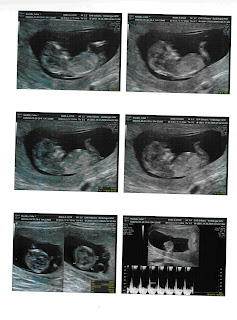

... ou melhor, 11 semanas e 5 dias e 53mm de gente a crescer dentro de mim! Tem uns pézinhos minimos que mal se vêem, o coração bate a 162/min, o estômago é visivel no local certo, o cérebro está formado e tem os dois hemisférios distintos e definidos... e mais coisas que só vendo.... eheheh

E não, infelizmente ainda não conseguimos saber se é munino ou munina... agora temos de esperar (todos) até dia 6 de Janeiro...

Vejam bem o que o/a malandreco/a anda a fazer... não admira que eu ande sempre cansada... lol

5ª feira de manhã é a primeira grande ecografia... :)